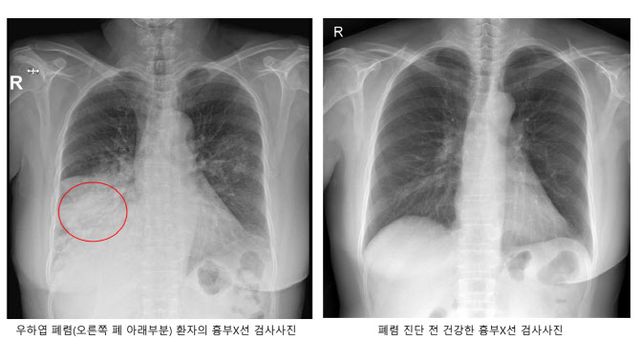

폐렴의 초기 증상은 발열, 기침, 가래 등 일반 감기와 비슷하다. 하지만 폐렴구균이 본격적인 활동을 시작하면 고열과 기침, 가슴통증, 호흡곤란을 유발한다. 숨이 가빠지면 호흡수도 많아져 분당 20회를 초과하는 것이 특징이다.

가톨릭대학교 서울성모병원 호흡기내과 민진수 교수는 “폐렴구균의 의한 폐렴일 경우 가래의 색깔이 적갈색으로 진하게 바뀌는 경우도 있다. 폐렴에 의해 폐가 손상되게 되면 산소교환 기능이 저하되게 되고, 그로인해 혈액 속에 산소 농도가 떨어진다. 이로 인해 입술이 푸른빛으로 변하는 ‘청색증’은 폐렴 합병증의 증상이다. 이 정도가 되면 생명이 위험할 수 있으므로 반드시 병원을 찾아야 한다”고 말했다.